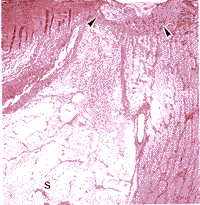

这例正常眼压性青光眼患者的视神经乳头和视网膜组织病理改变在左眼比右眼重,这与视乳头临床表现一致。双侧视神经乳头有明显的凹陷,具有筛板的排列紊乱、受压及后突等特征。通过视神经乳头的轴突数目减少并存在坚实的束状细胞外基质。然而在正常眼中筛板表现为规则的水平排列。正常眼压性青光眼患者的双眼视神经用Alcian蓝染色有空隙提示有Schnabel海绵状变性(图4)。在乳头旁的区域中,视网膜色素上皮、脉络膜毛细血管和光感受器均有萎缩(图2)。

图4 正常眼压性青光眼的视乳头。A,视乳头凹陷,筛板后弯(箭头)及右眼视乳头筛板前区(小箭状物)和筛板后区(大箭状物)的Schnabel海绵状变性(Masson三色计;原大×25)。B,左眼视神经筛板后区广泛的Schnabel海绵状变性(S)。可见筛板后弯(箭头)苏木精-伊红;原大×10)。C,左眼视神经海绵区(Alcian蓝;原大×25)